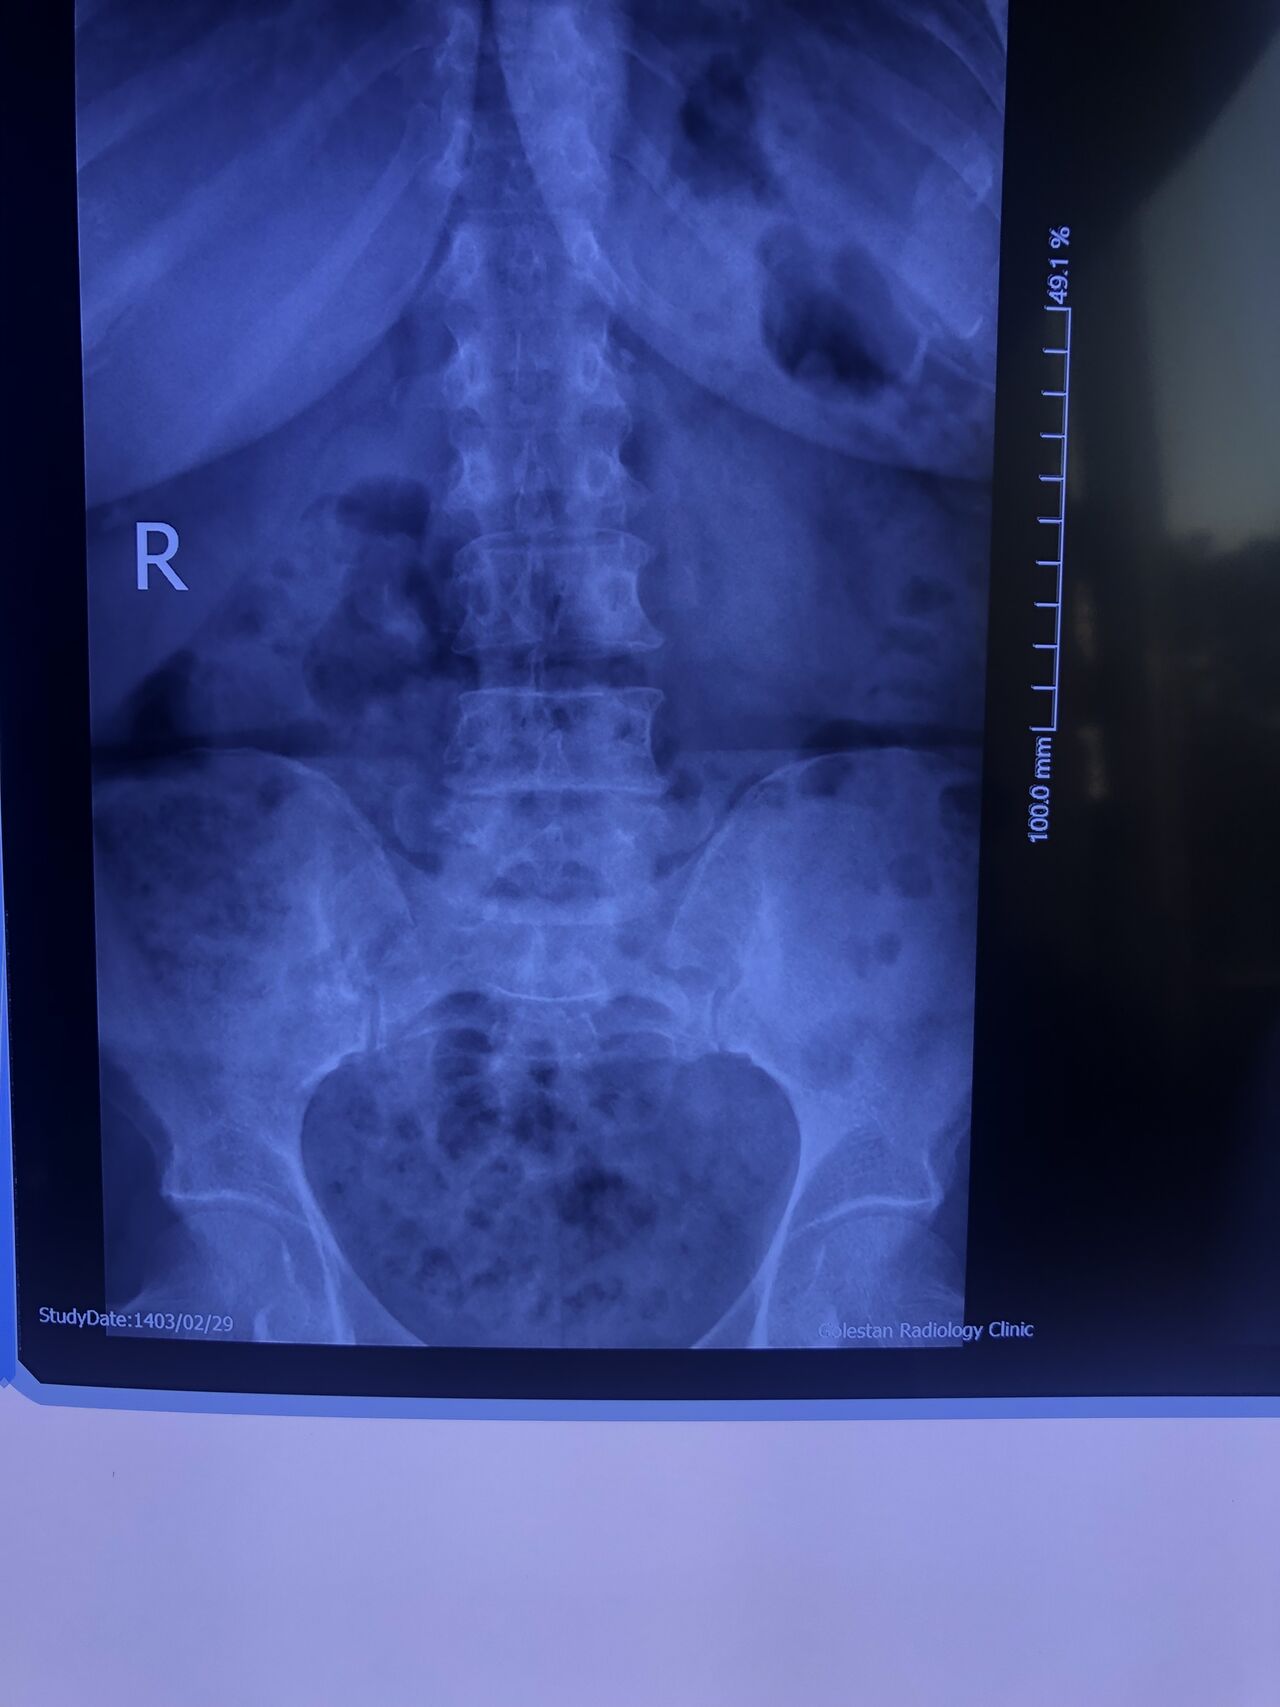

Case 7

60 years old female patient presented to my clinic today,

May 31/2025 with R. Chronic pelvic pain which gets aggravated by walking. Her lower extremity motors all were fine

L4-L5 level:

sever L4-5 canal stenosis mainly due to FL hypertrophy?

CSF block. Mild L3 retrolisthesis, facets hypertrophy bilateraly causing L and R IVF stenosis, disc hyperbule

Since I’ve noticed instability in some segments I asked for dynamic L/S x ray:we see mild L4 ant listens due to DjD/DDD. There is not any pars defect.